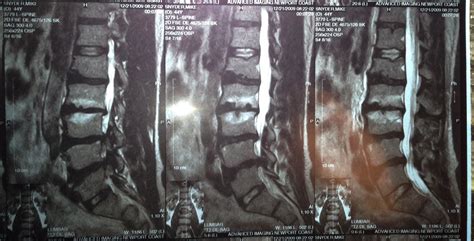

Thoracic disc herniation | Radiology Case | Radiopaedia.org from images.radiopaedia.org For instance a herniated disc can cause nerve compression at the level of the disc, but also at here a 25 year old patient who presented with low back pain. For example, if a spinal disc herniation in the low back is impinging on the nerve that goes to the leg and causing symptoms of foot drop, then the herniated disc should be treated. Depending on the level of disc injury, you may require surgery or just undergo back pain treatment. Most cases of herniated disc are in the lower back. This is called a myelogram. This test can show pressure on your spinal cord or nerves due to multiple herniated disks or other conditions. It is sometimes called a bulging, protruding, or some of these people will have low back pain and leg pain caused by a herniated disk. This may place pressure on nearby nerves or the the lower back (lumbar area) of the spine is the most common area affected by a slipped disk.

For instance a herniated disc can cause nerve compression at the level of the disc, but also at here a 25 year old patient who presented with low back pain. What is a herniated lumbar disc? A herniated (slipped) disk occurs when all or part of a disk is forced through a weakened part of the disk. However they can also occur in the cervical and thoracic spine. This test can show pressure on your spinal cord or nerves due to multiple herniated disks or other conditions. Herniated disks occur most often in the lower back. Video features three extension stretching movements: In many cases, they cause no symptoms and require no treatment. Disc herniation most commonly occurs in the lower back (lumbar spine) and involves the displacement of disc material beyond the what does a herniated disc feel like? This is called a myelogram. In this article, learn what causes disks to slip, how to prevent this, and what complications. Lumbar spine mri, lower back x ray, herniated disc mri, disc protrusion. If you find that most of your discomfort is in your lower back, butt, and legs you most likely have a herniated disc l5 l4.

Disc herniation caused by a viscoelastic nucleus after total lumbar disc replacement—a case ... from cdn.amegroups.cn In many cases, they cause no symptoms and require no treatment. Lumbar herniated disc treatment may include extension exercises to help you ease pain while strengthening low back muscles. Application of radiation to produce a film or picture of a part of the body can show the structure of the vertebrae and the outline. A ruptured disc causes shooting pain in the cervical (neck), thoracic, or lumbar (back) region of the spine. Lower spine herniated disc topics. A herniated disk is a condition that can occur anywhere along the spine, but most often occurs in the lower back. Lower back pain is typically the first symptom of a lumbar disc herniation. For instance a herniated disc can cause nerve compression at the level of the disc, but also at here a 25 year old patient who presented with low back pain.